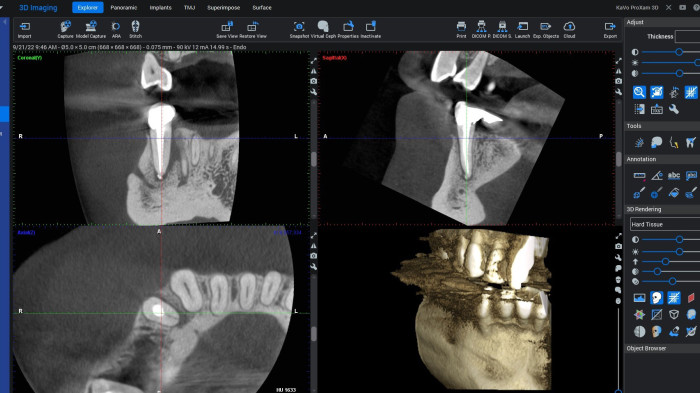

Możliwości oraz ograniczenia obrazowania 2D i 3D – kiedy i jakie badanie należy zlecić pamiętając o zasadzie ALARA. Jakość badania RTG – co na nią wpływa, jak ją oceniać, jak wyeliminować potencjalne błędy rzutujące na obniżenie jakości badań radiologicznych. Poruszanie się po badaniu CBCT – możliwości oceny tkanek oraz stanów patologicznych poprzez wyświetlanie badania w formie przekroi, rekonstrukcji wolumetrycznej, rekonstrukcji badań 2D (MPR – multi planar reconstruction). Mnogość narzędzi w oprogramowaniu KaVo RTG – jak efektywnie wykorzystywać je na co dzień w poszczególnych przypadkach z zakresu chirurgii, endodoncji, ortodoncji, etc.

Dokonywanie pomiarów, planowanie położenia wszczepów implantologicznych, lokalizacja kanałów dodatkowych, zębów zatrzymanych oraz inne zagadnienia diagnostyczne spotykane na co dzień w praktyce stomatologa. Podstawy oceny badań RTG w obrębie stomatologii.

Podczas webinaru pokażemy, jak w pełni wykorzystać dane z badań 2D i 3D, jak sprawnie poruszać się po badaniu CBCT oraz jak szybko odnajdywać kluczowe struktury anatomiczne i zmiany patologiczne. Uczestnicy nauczą się wykonywać precyzyjne pomiary, analizować przekroje, rekonstrukcje wolumetryczne oraz MPR, a także wykorzystywać te informacje w planowaniu leczenia.

• Praktyczne triki pracy z badaniem CBCT (MPR, rekonstrukcje, przekroje)

• Pomiary, planowanie implantologiczne, lokalizacja kanałów dodatkowych i zębów zatrzymanych